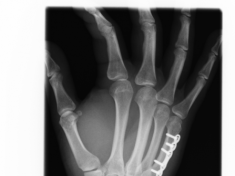

Röntgenbilder